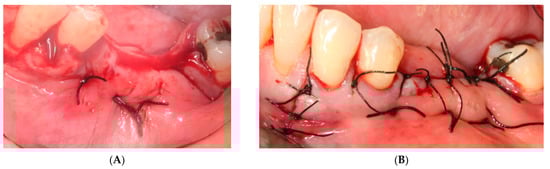

- First surgery: Local anesthesia Articaine 4% with epinephrine (1:100,000) was administered. An intrasulcular incision was made from the mesial of 3.3 to the distal of 3.7, continuing along the anterior border of the external ramus of the mandible. Periosteal incisions were made to mobilize the vestibular flap and the upper fibers of the mylohyoid muscle were disinserted to passivate the lingual flap and thus obtain a tension-free closure (Figure 3). We then checked the position of the mesh and proceeded to collect bone from the ascending branch using the bone scraper (Micross®, Selecdent, Barcelona, Spain) (Figure 4A). Cortical perforations were made to promote bleeding (Figure 4B). We mixed the autologous bone with the xenograft (Tioss®, Sanhigia, Bujaraloz, Spain) in a 70:30 ratio, inserted it into the mesh, and the mesh was placed in the defect.